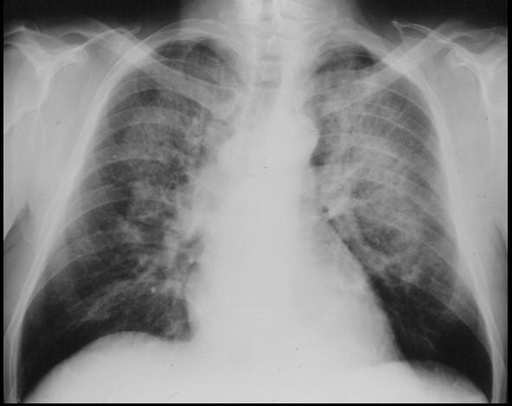

Imagerie du thorax

E. COCHE - UCL

Année académique 2025 - 2026

IPL - manipulateurs en imagerie

Cardio-thoracique

Poumon